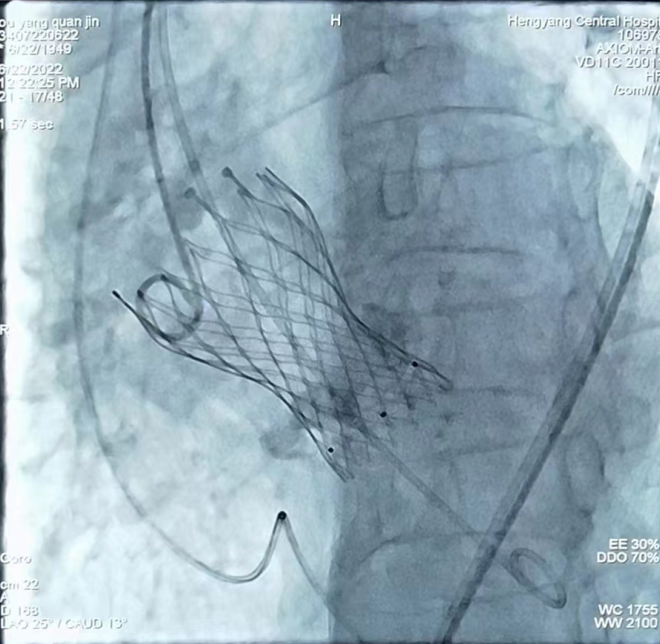

心內(nèi)一區(qū)通訊員何紅丹報道:為推進結(jié)構(gòu)心臟病介入這一先進技術的開展,我院組建了以心血管內(nèi)科為主導的TAVR手術團隊,其中包括胸心外科、麻醉科、ICU、手術室、超聲科專家。6月22日上午,我院在心血管內(nèi)科趙慶禧主任醫(yī)師手術組及TAVR團隊的通力合作下,又成功開展一例TAVR手術,標志著我院TAVR團隊在技術積累、流程優(yōu)化和團隊建設取得重大突破,是我院TAVR技術成熟的一個里程碑。

患者為73歲老年女性患者,心臟彩超示主動脈瓣重度狹窄伴輕中度反流,冠狀動脈CTA示冠狀動脈硬化,主動脈瓣多發(fā)鈣化,右冠狀動脈近、中段管壁鈣化,管腔稍窄。結(jié)合患者年齡大、心功能差,不能耐受開胸換瓣等實際情況,趙慶禧主任組織TAVR團隊對患者進行了縝密的術前討論,充分評估了患者主動脈瓣及冠脈的情況,并與患者及家屬進行了充分溝通,經(jīng)過反復研討,制定了一套精密的手術方案。手術過程歷時3個小時,患者術中術后生命體征平穩(wěn),目前正處于康復階段。

TAVR手術即經(jīng)導管主動脈瓣置換手術,是一種通過微創(chuàng)介入導管,將人工心臟瓣膜輸送至主動脈瓣區(qū)域并釋放,完成人工瓣膜置入,治療主動脈瓣狹窄的手術。TAVR手術具有創(chuàng)傷小、術后恢復快等優(yōu)點,使得部分以前無法行開胸瓣膜置換的患者成功進行瓣膜置換成為可能。隨著我院TAVR手術團隊臨床經(jīng)驗的豐富和器械的不斷發(fā)展,TAVR手術在我院越來越成熟,標志著我院的心臟瓣膜置換進入微創(chuàng)時代,為更多的老年、高危、復雜性心臟瓣膜病患者帶來“心”的希望,為衡陽乃至湘南地區(qū)老百姓的健康帶來了福音。